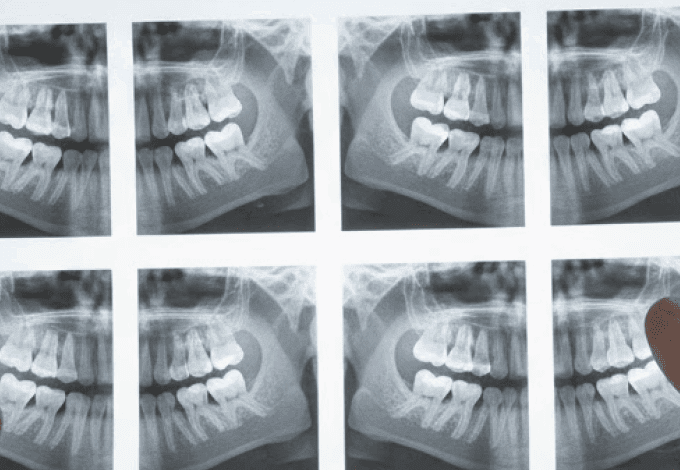

A Dental Speed, em parceria com a ABIMO, marcou presença no evento que movimentou a capital paulista com distribuição de kits e o...